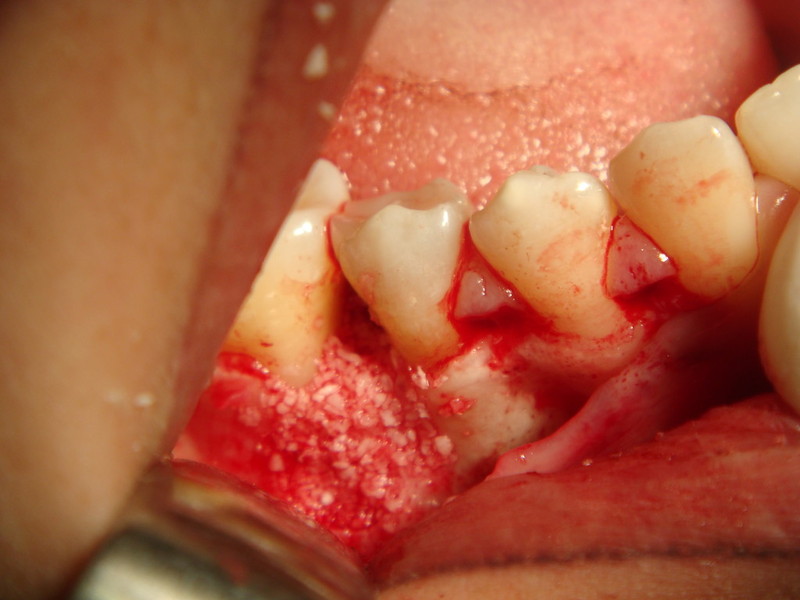

rigenerazione grave difetto parodontale a carico del 46